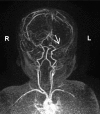

Prenatal ultrasonographic detection of unilateral cerebral ventriculomegaly arises suspicion of pathological condition related to cerebrospinal fluid flow obstruction or cerebral parenchimal pathology. Dyke-Davidoff-Masson syndrome is a rare condition characterized by cerebral hemiatrophy, calvarial thickening, skull and facial asymmetry, contralateral hemiparesis, cognitive impairment and seizures. Congenital and acquired types are recognized and have been described, mainly in late childhood, adolescence and adult ages. We describe a female infant with prenatal diagnosis of unilateral left ventriculomegaly in which early brain MRI and contrast enhanced-MRI angiography, showed cerebral left hemiatrophy associated with reduced caliber of the left middle cerebral artery revealing the characteristic findings of the Dyke-Davidoff-Masson syndrome. Prenatal imaging, cerebral vascular anomaly responsible for the cerebral hemiatrophy and the early clinical evolution have never been described before in such a young child and complete the acquired clinical descriptions in older children. Differential diagnosis, genetic investigations, neurophysiologic assessments, short term clinical and developmental follow up are described. Dyke-Davidoff-Masson syndrome must be ruled out in differential diagnosis of fetal unilateral ventriculomegaly. Early clinical assessment, differential diagnosis and cerebral imaging including cerebral MRI angiography allow the clinicians to diagnose also in early infancy this rare condition.